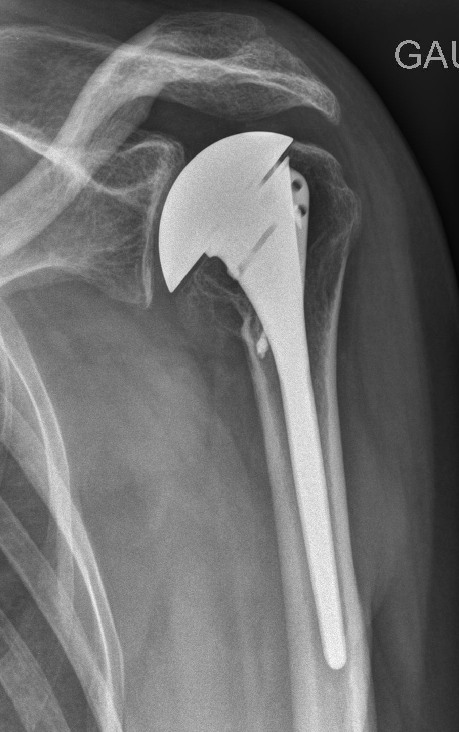

Prothèse humérale simple

La tige est commune à toutes les configurations de prothèse (humérale simple, anatomique, inversée). Elle est dite « modulaire ».

La configuration de chaque humérus diffère et la portion de sphère doit couvrir au mieux la tranche de section osseuse afin de ne pas rentrer en conflit avec les tendons de la coiffe.

Figure 1 : cas d’une configuration nécessitant une tête centrée

Figure 2 : cas d’une configuration nécessitant une configuration excentrée avec couverture essentiellement antérieure (proche du relief de la petite tubérosité)

L’impaction de la tige se fait si possible sans scellement par ciment chirurgical, on réalise alors une greffe de la zone métaphysaire de l’humérus (partie large sous la tête) ou la tige est recouverte d’une couche ostéo-intégrable (permet de s’accrocher à l’os). L’os spongieux nécessaire est prélevé dans le creux de la tête humérale retirée.

Un scellement par ciment est préférable chez la personne agée ou bien en cas de tenue primaire moyenne des implants.